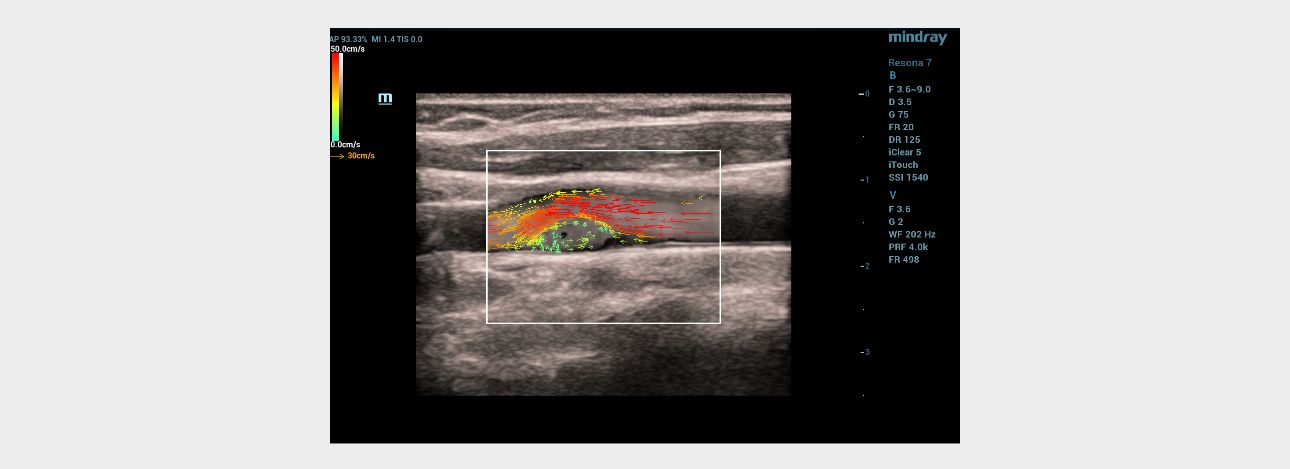

Ultrasound examination – vector analysis of blood flow mode (V Flow)

When the vector analysis mode (V Flow) was activated, the complete filling of the lumen of the left common carotid artery in the bifurcation area with colored vector arrows was clearly traced. The following changes were registered immediately after the linear hyperechoic structure: 1) shorter color arrows compared to arrows from the main blood flow in the vessel; 2) the arrows had a different color pattern (green, blue, yellow) in contrast to the red and orange arrows of the main stream; 3) the short arrows had a multidirectional, vortex-like direction in contrast to the laminar flow, which was determined over the pathological area of the vessel with a hyperechoic linear structure (Fig. 4). Given the absence of signs of flotation of hyperechoic linear formations and the topical symmetry of the location, it was assumed that these changes are characteristic of the carotid web.

aotid-web-v-flow-fig4-pc

Fig 4. Ultrasound of the carotid sinus using the V Flow mode.

Ultrasound vector analysis of blood flow

The V Flow mode made it possible to clearly see the full filling of the vessel lumen with colored arrows directly behind the hyperechoic linear formation on the left. The direction, color and size of the arrows in this area of interest clearly provided information about the slow-speed, retrograde and then vortex-like flow of blood in the vessel, which explained the poor color filling of the vessel lumen directly behind the hyperechoic linear structure in the color Doppler mapping mode, due to the high dependence of the latter on the speed and direction of moving blood particles (erythrocytes). The technology of vector analysis of blood flow made it possible to exclude the presence of an atherosclerotic plaque or a parietal thrombus.